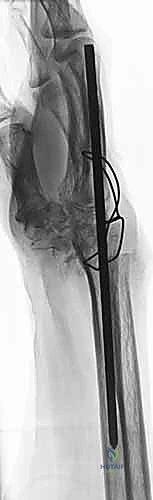

Operative Techniques in Orthopaedic Surgery